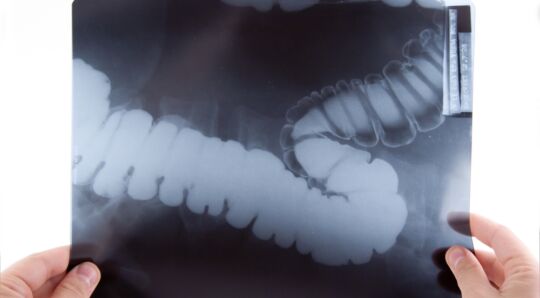

Chronic abdominal pain is common in primary care, but diagnostic imaging is often not needed . When imaging is indicated, a CT scan may not be the ideal investigation. Ultrasound, CT and MRI all have their advantages and disadvantages.